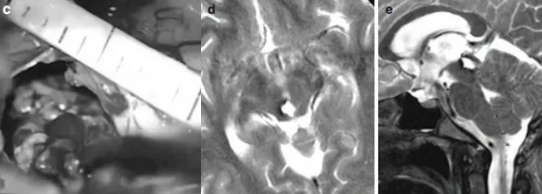

面对喜喜此时的情况,当务之急是缓解脑积水症状。于是,巴教授立即进行了内镜下第三脑室造痿术,术后喜喜无任何并发症,也没有再出现癫痫发作。

于是没过不久,巴教授再次为喜喜主刀手术。巴教授选择经幕下小脑上入路暴露病变,术中发现病变为典型的海绵状血管瘤,而且还出现了新鲜的病灶内出血,很难想象如果没有及时手术,喜喜又将面临怎样的危急时刻。

所幸,手术最终成功全切脑海绵状血管瘤,术后喜喜的恢复情况令人欣慰,没有出现任何术后并发症,在乐观的家庭氛围感染下,当初那个爱笑的女孩又回来了!